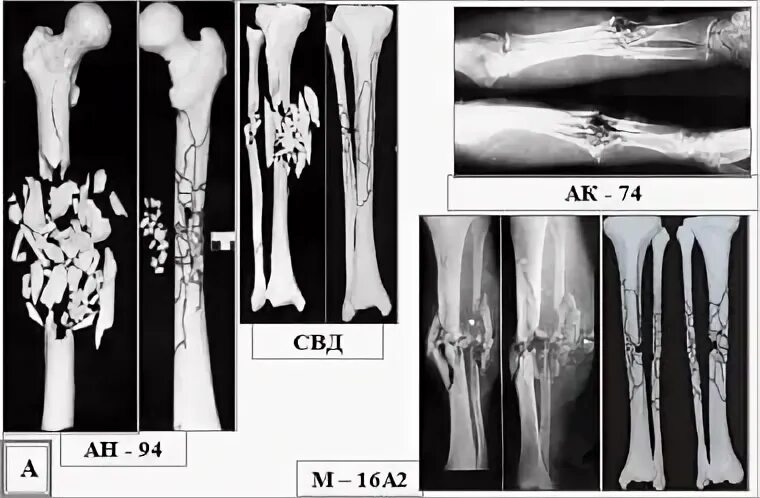

Разрушение мягких тканей